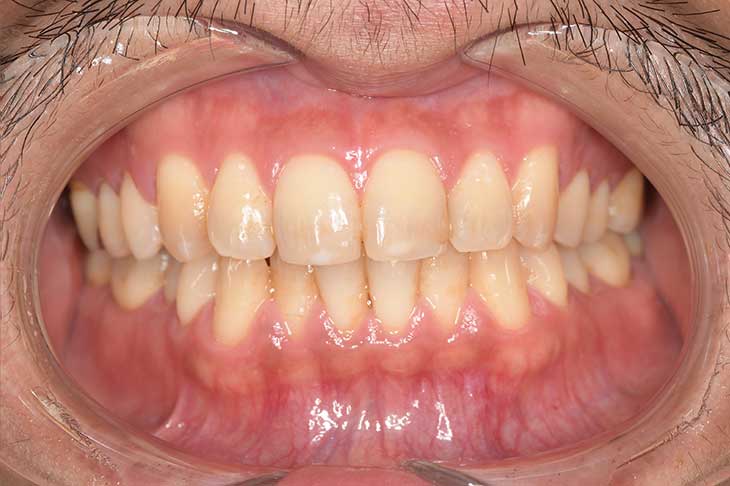

CASE 4

Before

After

基本情報

| 年齢・性別 | 52歳・女性 |

| 主訴 | クリーニングしたい |

| 治療内容 | スケーリング・PMTC |

| 治療期間 | 60分 |

| 治療費 | 約7,000円 |

| リスク・副作用 | 知覚過敏、歯肉退縮 |

| 治療方針 | 歯石とステインを除去して、今後は定期検診でのクリーニングと併せてガムピーリングやホワイトニングを行います。 |

| 担当者所見 | 歯肉の色素沈着が目立つため、ガムピーリングを行いながらホワイトニングを行うことをおすすめします。 |